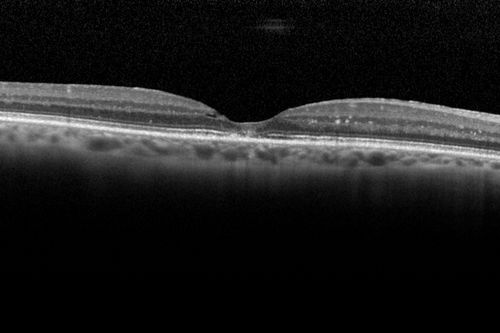

Macroaneurysm - Resolved without treatment

87 year old female with vision loss OD. Initial FA showed no leakage so no treatment was done and the fluid absorbed over 4 months. Initial VA 20/100, Final VA 20/80